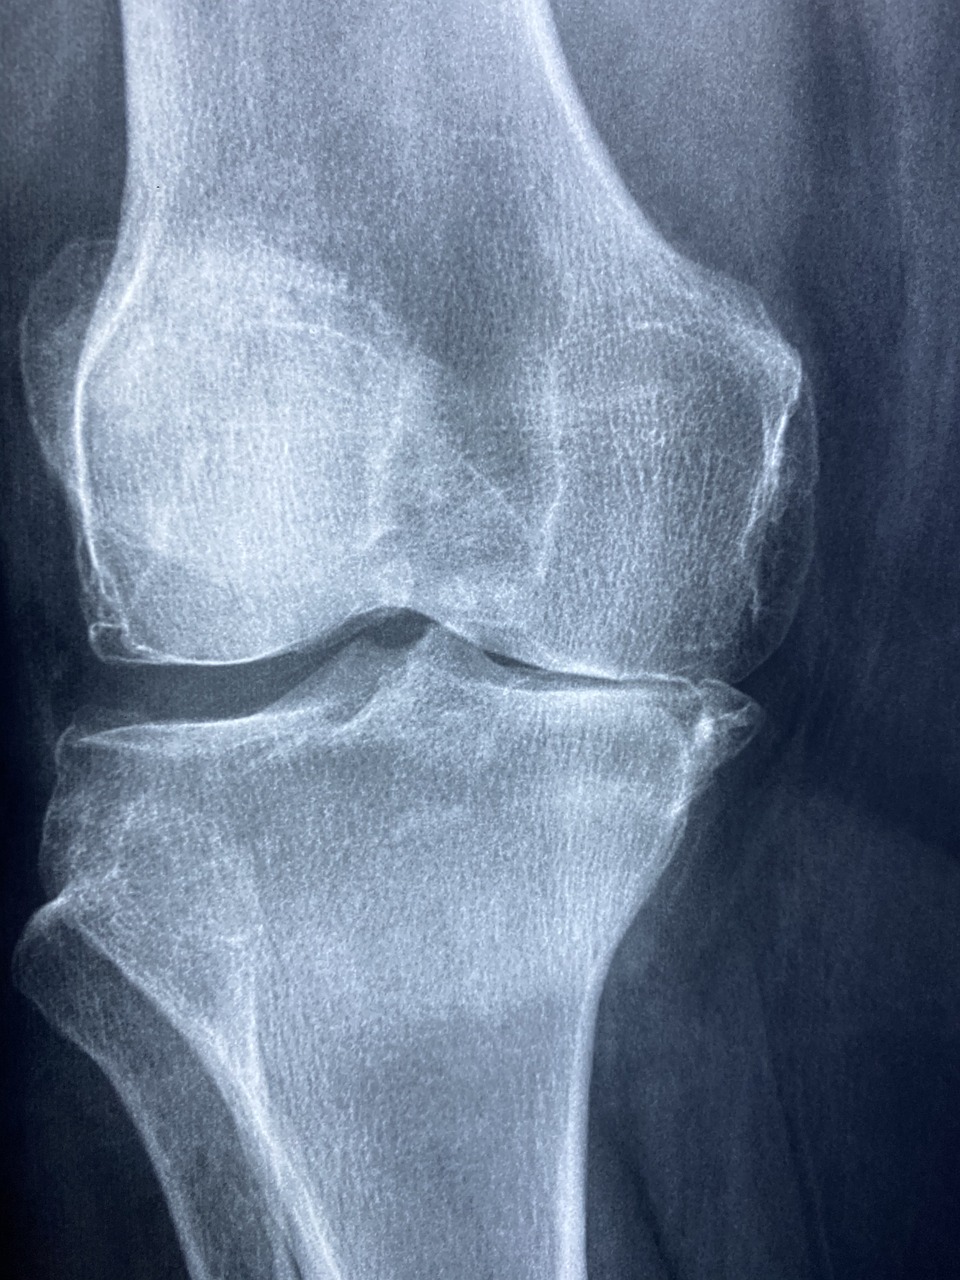

콘드로이친(Chondroitin)은 관절을 보호하는 중요한 성분으로, 연골 조직의 수분과 탄력을 유지하는 역할을 합니다. 특히 관절염, 연골 손상, 무릎 통증이 있는 사람들에게 필수적인 영양소로 알려져 있습니다. 콘드로이친의 효능, 부작용, 복용법을 완벽하게 정리되었으니 꼼꼼하게 확인하세요!

1. 연골 보호 & 관절 건강 개선

✔ 콘드로이친은 연골의 수분을 유지하고 탄력을 높여 관절을 보호하는 역할을 합니다.

✔ 퇴행성 관절염(골관절염) 환자의 통증을 완화하는 효과가 있습니다.

✔ 무릎 관절뿐만 아니라 손목, 어깨, 허리 관절 건강에도 도움을 줍니다.